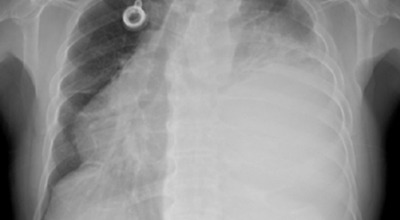

폐암 검사는 주로 X-ray를 통해 이루어지지만, 종양의 크기가 작거나 구석에 위치한 경우에는 확인이 어려운 경우도 있습니다. 그 후, 조직 검사를 통해 정확한 진단을 하게 됩니다. 폐암이 발견되면, 종양의 크기, 전이 여부, 위치에 따라 수술 여부를 결정하게 됩니다.

수술 치료

악성 종양이 있는 폐의 일부를 절제하는 방법으로, 초기 단계에서는 내시경 기구를 활용하여 수술이 가능하기도 합니다.